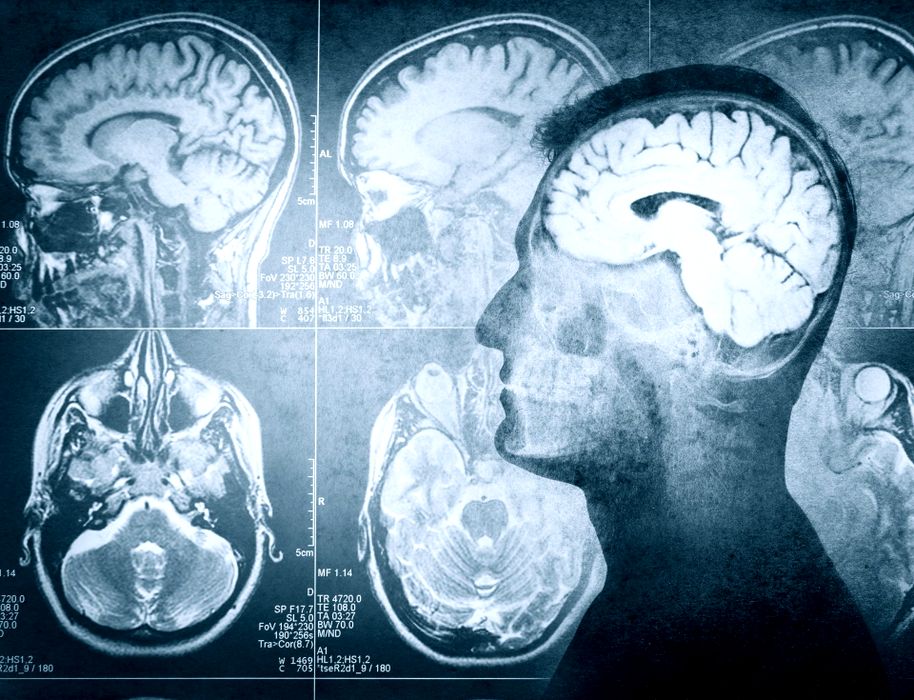

Adulții cu TSA sau sindrom Down suferă mai mult de anxietate și depresie

Adulții cu TSA sau sindrom Down suferă mai mult de anxietate și depresie. Aceștia se confruntă cu rate mult mai ridicate de anxietate și depresie decât populația generală. Descoperirile au fost publicate în JAMA Network […]